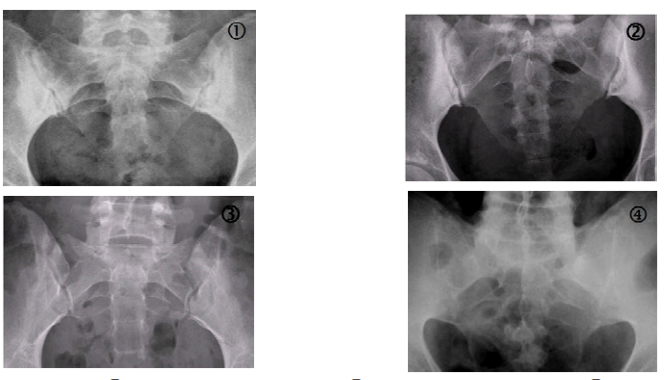

27 下列骶髂關節區(sacroiliac joint region)的 X 光圖形,何者屬於僵直性脊椎炎(ankylosing spondylitis) 的表現?

(A)① (B)② (C)③ (D)④